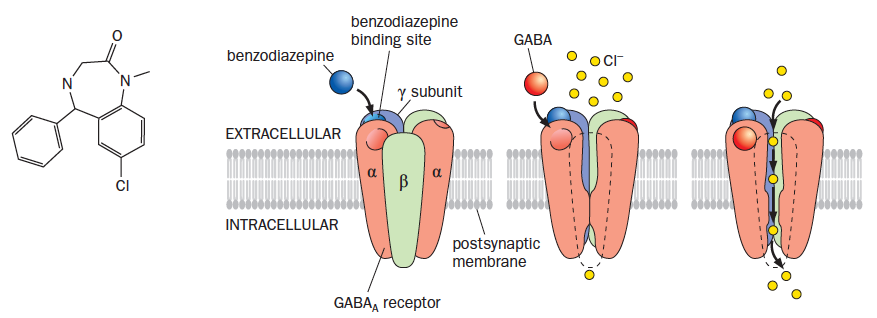

Anxiety disorders

- Most common types of psychiatric disorders, include anxiety, phobias, panic disorders, obsessive-compulsive disorder

- Often associated with fatigue, muscle tension, and sleep disturbance. 5% of people report some type of general anxiety disorder

- Barbiturates– reduce anxiety but also are potent sedatives. Overdose is lethal

- Benzodiazepines– reduce anxiety without as much sedation. Harder to overdose on benzodiazepines

- Both drugs bind to the ionotropic GABA receptors and enhance GABA transmission

Benzodiazepine mechanism of action

- Benzodiazepines increase the affinity of the receptor for GABA

- Barbituates can activate the GABA receptor independent of GABA

Note:

Act at the level at the interface of the alpha and gamma subunits. Different neurons express different gamma subunits. Six different genes for the alpha subunit. Benzodiazepines only can interact with the a1,a2, and a5 subunits, have a conserved histidine.